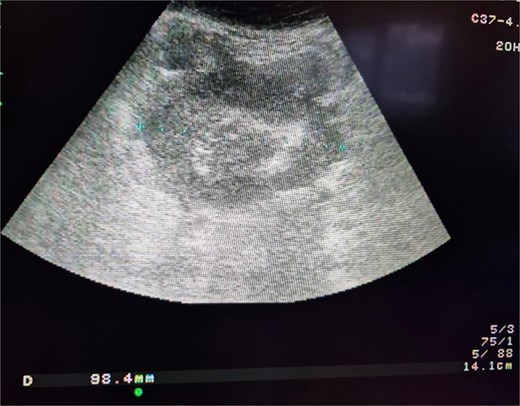

A 74-year-old woman complains of severe constipation, difficult to respond to laxatives and abdominal pain, nausea. A primary abdominal ultrasound (US) examination revealed a hypoechoic tumor formation in the lower abdomen, with uneven outlines and hyperechoic zones in it, with dimensions of ~10 cm/day (Fig. 1). The patient was referred for a computed tomography (CT) scan of the abdomen, which revealed a soft tissue formation with axial dimensions of 130/93 mm heterogeneous structure and infiltrative growth, affecting a segment of the ileum and an adjacent dilated small intestinal loop (Fig. 2). Secondary dissemination along the peritoneum with many soft tissue formations of different sizes formed in the abdomen and small pelvis. Identical lesions are described in the structures of both ovaries bilaterally, the larger of which is 47/34 mm/day. Laboratory parameters revealed anemia with values of Hg-103 g/L, and low values of total protein-60 g/L. The patient has a history of Hashimoto’s thyroiditis and is on replacement therapy with L-thyroxine. During hospitalization, she showed good compensation with a slightly increased TSH- 4.88 mU/L (normal 0.27–4.2) and normal FT4–17.7 pmol/L (normal 12–22). Tumor markers CEA, CA 125, and CA 19-9 were not elevated.

Abdominal CT showing small bowel tumor and similar to both ovaries.